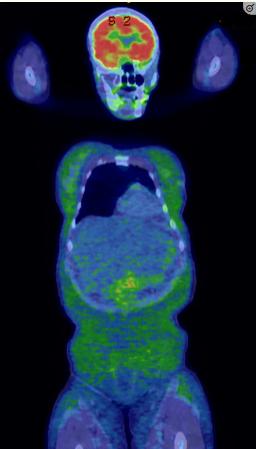

除了新发糖尿病,患者还出现了新的代谢异常,包括高甘油三酯血症436mg/dL(4.93 mmol/L)[参考范围:< 150 mg/dL (<1.7 mmol/L)]和肝酶升高(正常上限的3-4倍)。随后的肝活检显示严重的大泡性脂肪变性,没有任何脂肪性肝炎的证据。值得注意的是,在初始评估期间测量的血清瘦素浓度无法检测到<0.6 ng/mL (参考范围:3.3-18.3 ng/mL)。用于癌症监测的全身FDG-PET显示整个皮下组织存在轻度弥漫性FDG活动,提示为脂膜炎(图2)。然而,临床上没有提示脂膜炎的迹象。在接下来的3个月里,体重减轻了20公斤,并伴有从头至脚的全身皮下脂肪减少(图1和3)并继续具有显著的低瘦素血症。

图2、全身FDG-PET扫描显示弥漫性轻度皮下FDG活动,提示脂膜炎